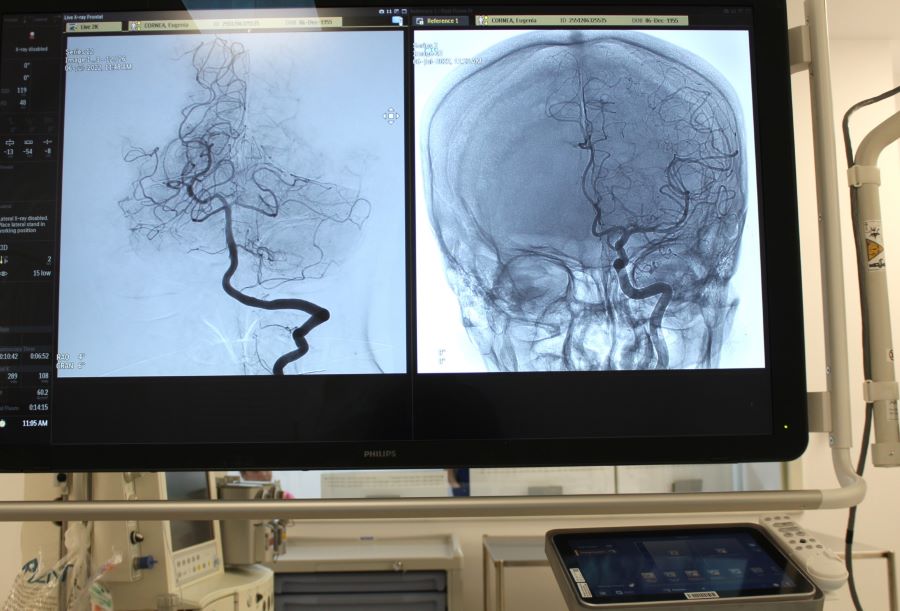

Județul Sibiu are șansa de a avea unul din cele nouă centre naționale acreditate în tratamentul endovascular al accidentului vascular cerebral (AVC), funcțional în cadrul Spitalului Clinic Județean de Urgență Sibiu. Pentru dotarea acestuia, unitatea medicală, cu sprijinul Consiliului Județean Sibiu, a achiziționat în anul 2022 primul angiograf biplan cu ajutorul căruia sunt efectuate intervenții de îndepărtare a cheagurilor care obturează vasele de sânge sau sunt introduse stenturi.

Astăzi, în Sistemul Electronic pentru Achiziții Publice (SEAP) a fost lansată o licitație publică pentru achiziționarea celui de-al doilea angiograf, cu o valoare estimată de 9,09 milioane lei. Termenul de depunere a ofertelor este 3 martie 2026.

Investițiile vor crește capacitatea de reacție a medicilor sibieni în cazul pacienților cu AVC, în condițiile în care șansele de recuperare totală sunt maxime dacă intervenția este efectuată în primele 6 ore de la atac.